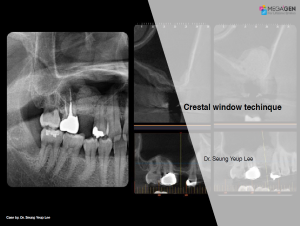

Dr. Achraf Souayah,Edentulous,Aesthetic zone,Maxillary Anterior,Maxillary Posterior,Mandibular Anterior,Mandibular Posterior,Guided surgery,Sinus Elevation,Immediate Placement,AnyRidge,Overdenture system,Meg-Rhein,MILA Kit,Clinical case